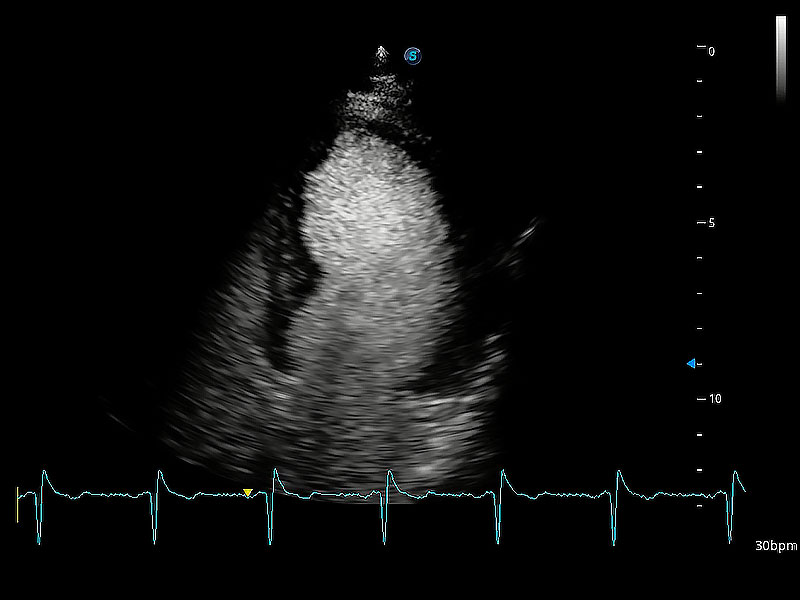

ProPet 80 配備了豐富的心臟探頭群、先進(jìn)的成像技術(shù)和專業(yè)的心臟測量工具,可幫助動物醫(yī)生為不同體型和生理結(jié)構(gòu)的動物提供心臟和心肌功能的全面評估。

能夠基于左心室壁追蹤和辛普森法,自動計算射血分?jǐn)?shù),支持多個可移動點(diǎn)描跡,與手動測量相比,極大節(jié)省了動物醫(yī)生的時間和精力。